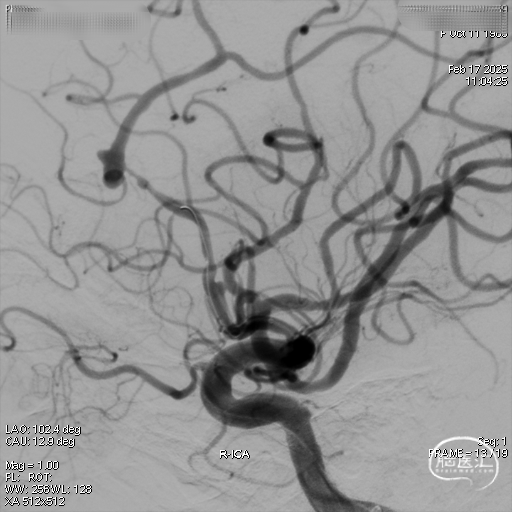

右侧颈内正位造影

右侧颈内侧位造影

载瘤动脉远端血管直径:2.1mm

载瘤动脉近端血管直径:1.8mm

动脉瘤尺寸:瘤颈4.69mm,大小3.25mm*4.21mm*4.24mm;指向右上

近端狭窄:最窄处:0.53mm,远心端2.1mm,近心端2.2mm,长度11.23mm

术后造影。

术后正侧位造影。

强易达(Choydar)血流导向密网支架材质是镍钛合金,输送易到位;头端导丝、50%释放点、100%释放点清晰,便于观察支架位置。

50%Mark点可帮助分析后半段打开后的尾端位置,近端血管较粗考虑支架短缩,也可调整支架的50%Mark点置于偏近端一些。

支架由2对4根铂钨合金显影丝以对向排列的方式,混合编入支架主体,呈3D立体显影效果,便于观察支架贴壁情况。